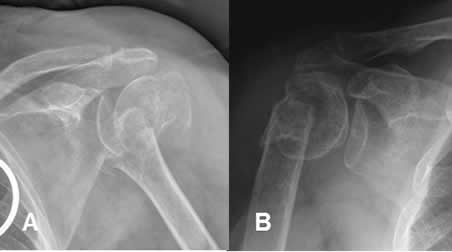

Fig 49. Fractura impactada.

A y B: Rx AP de hombro. Fracturas impactadas y con diferente grado de desplazamiento de la cabeza humeral.